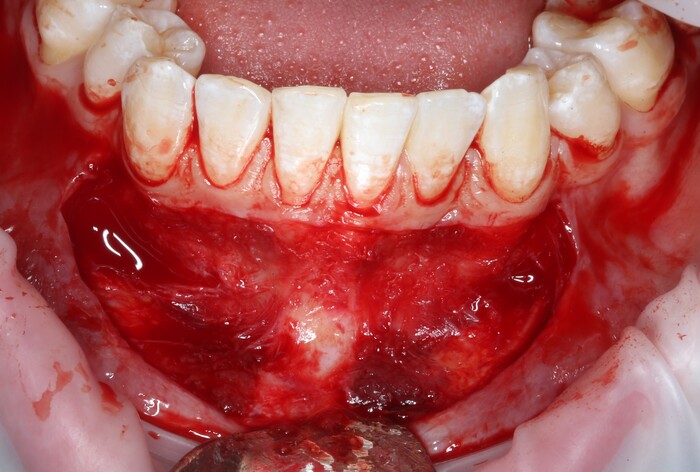

2 – проведение пластики десны.

Был взят трансплантат в области бугра верхней челюсти (это то место, где раньше был зуб мудрости).

Далее проведена пластика десны, снова два месяца ожиданий и установка временной коронки: